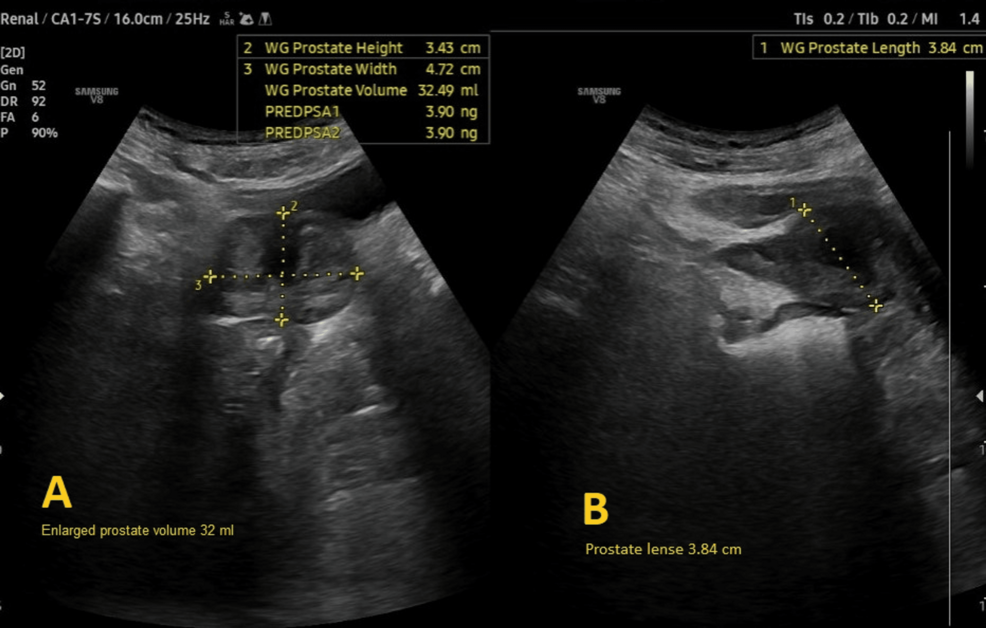

Preoperative evaluation classified the patient as American Society of Anesthesiologists (ASA) physical status 3, reflecting severe systemic disease. The Revised Cardiac Risk Index (RCRI) score indicated Class III, with a major adverse cardiac event risk exceeding 10.1% [4]. Electrocardiography showed sinus rhythm with right bundle branch block (Figure 2), while chest radiography was unremarkable. Airway assessment revealed a Mallampati Class II score, full cervical mobility, and removable partial dentures. Laboratory findings (Table 1) included elevated serum creatinine (4.98 mg/dL), mild hyperkalemia (5.7 mmol/L), mild anemia (hemoglobin of 11.6 g/dL), and a normal international normalized ratio (INR: 1.00). Imaging confirmed the femoral neck fracture, with ultrasonography noting renal cysts (Figure 3) and prostatic enlargement (Figure 4). An echocardiogram was normal (Figure 5). Cardiology consultation advised continuing bisoprolol, resuming aspirin postoperatively, and bridging anticoagulation with enoxaparin, discontinued 24 hours preoperatively. Recent hemodialysis stabilized electrolytes, optimizing the patient for surgery.